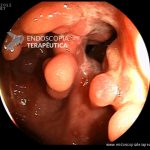

- Doença de Crohn em remissão – pseudopólipo